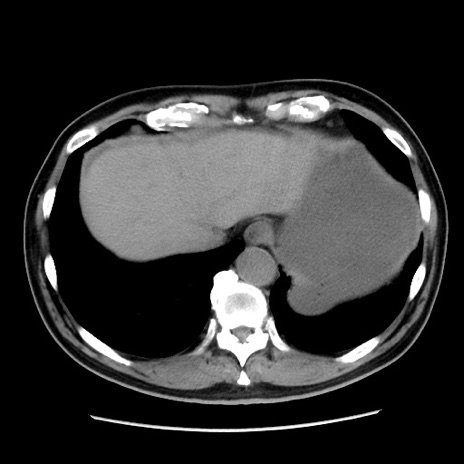

症例16(横断像)

【症例】 70歳代男性

【主訴】 腹痛、嘔吐

【現病歴】 約1ヶ月前より間欠的に腹痛と嘔吐あり、当院消化器内科を受診したところCTで多発する肝臓のLDAを指摘され、精査中であった。以降は消化器症状は安定していたが、2日前より嘔気と腹痛があり、同日より排便・排ガスが消失した。改善認めず、 本日、救急外来を受診した。

【既往歴】 大腸ポリープ切除後。

【身体所見】意識清明・会話良好、BT 36.3℃、BP 127/80mmHg、 P 80bpm、腹部:膨満あり、平坦・軟、上腹部正中および下腹部正中に圧痛あり、反跳痛なし、筋性防御なし。

【データ】WBC 7200、CRP 0.77